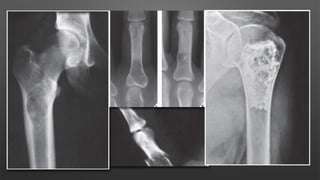

Giant Cell Tumor

• A benign aggressive tumor typically found in the metaphysis of long bones

• Age & sex

• more common in females

• ages 30-50 years

• Location

• distal femur > proximal tibia > distal radius > sacral ala

• distal radius is third most common location

• phalanges of the hand is also a very common location

• Malignancy

• primary malignant giant cell tumor

• metastatic to lung in 2-5%

• hand lesions have greater chance of metastasis

• secondary malignant giant cell tumor

• occurs following radiation or multiple resections of giant cell tumor